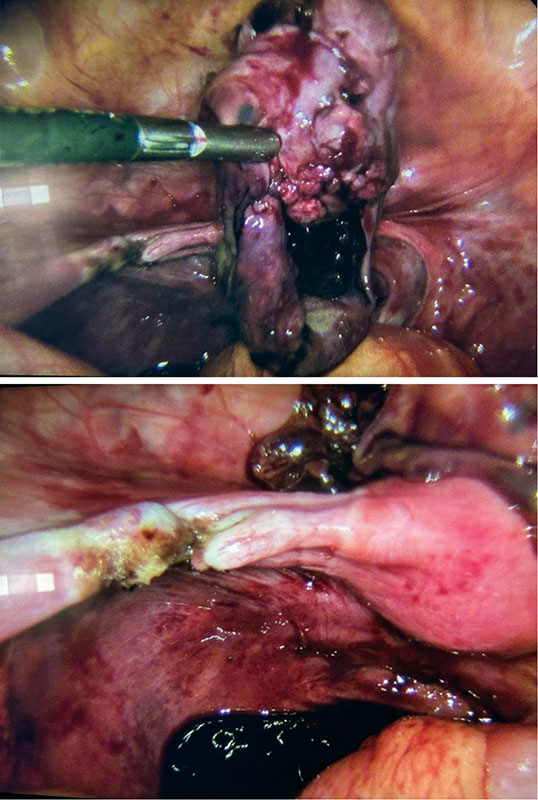

Рис. 6. Пациентка В., 13 лет: интраоперационная картина мягкого (нетугого) перекрута правых придатков матки

Рис. 7. Пациентка В., 13 лет: интраоперационная картина после деторсии правых придатков матки. Визуализируется лимфостаз в проекции правого яичника

Интраоперационно обнаружен мягкий перекрут правых придатков матки на 180° вокруг собственной оси с вовлечением правого яичника за счет округлого образования диаметром до 12 см (рис. 6). Левые придатки матки без особенностей. Тело матки нормального размера, серозный покров гладкий, блестящий.

С помощью зажимов проведены деторсия правых придатков матки и цистэктомия справа с использованием биполярной коагуляции (рис. 7). Удаленное образование извлечено из брюшной полости в эндобаге. Макропрепарат: cтенка кисты гладкая, содержимое прозрачное.